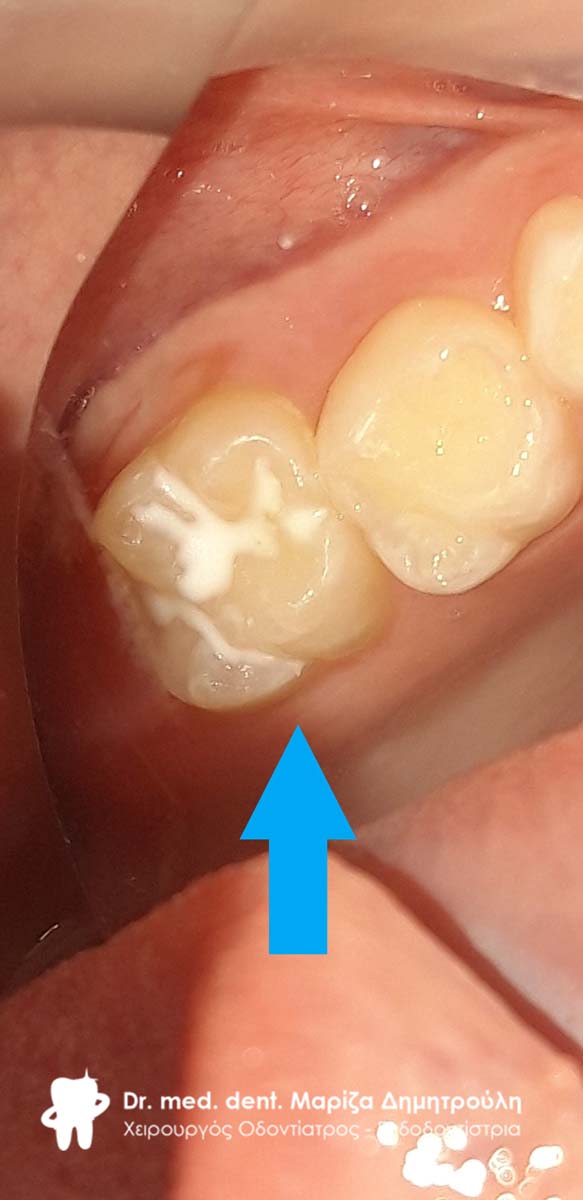

Στα πλαίσια του τυπικού οδοντιατρικού ελέγχου διαπιστώθηκε η ύπαρξη μιας μικρής τερηδονικής κοιλότητας στον πρώτο αριστερό μόνιμο γομφίο. Αποφασίστηκε η αφαίρεση της επιφανειακής αρχόμενης τερηδόνας και προληπτική κάλυψη οπών και σχισμών (sealant) στη μασητική επιφάνεια του μόνιμου άνω αριστερού πρώτου γομφίου.

Στο συγκεκριμένο ασθενή πραγματοποιήθηκε ταυτόχρονα αφαίρεση της επιφανειακής αρχόμενης τερηδόνας και προληπτική κάλυψη οπών και σχισμών (sealant) στη μασητική επιφάνεια του άνω αριστερού πρώτου γομφίου.